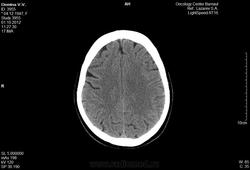

Женщина 64-х лет.

Диагноз:

Метостаз в правой теменной кости без первичного очага.Предложена лучевая терапия. Описание снимка: форма и размеры черепа обычные, в теменной кости определяется деструкция костной ткани без четких контуров размером 16мм.

Замыкательные пластинки истончены. Определяется снижение пневмотизации правой гайморовой пазухи за счет утолщения слизистой, слева на нижней стенке гиподесное образование с ровными контурами размером 22мм. Вещество мозга однородной структуры в симметричных участках плотность одинаковая. Среденные образования не смещены. Определяется неравномерное расширение субарахноидальных пространств и усиление борозд больше в лобных и теменных областях.

Заключение:

Наружная гидроцефалия, метостаз в теменную кость, киста левой гаиморовой пазухи, гайморит справа.

Пожалуйста, проконсультируйте в отношении заключения, верно ли оно?

///верно ли оно?/// Признаков гидроцефалии нет никаких, непонятно на основании чего поставлен гайморит справа, киста в левой верхнечелюстной пазухе есть. По этим снимкам (в этом режиме/окне) оценить состяние костей не представляется возсожным. Скопируйтк с диска dicom-изображения, сархивируйте их, разместите на любом файлообменнике, разместите здесь ссылку. Тогда можно будет посмотреть детальнее.

Согласна, в головном мозге - норма. Кости не показаны, надо смотреть. Гайморит сомнителен, надо смотреть в костном режиме.

Наружная гидроцефалия явно надумана за счет верхних нормальных для возраста срезов, а метастаз в кости не определяется в данном окне.

По этим снимкам невозможно оценить, что там в костях. Нужен DICOM. В мозге - умеренная атрофия, соответствующая возрасту.